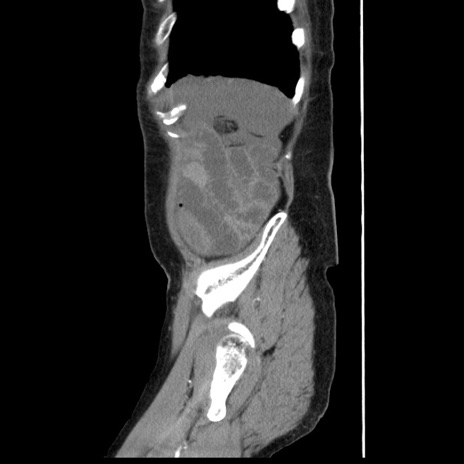

症例1(矢状断像)

【症例】80歳代女性

【主訴】腹痛

【現病歴】8時間前から腹痛あり来院。

【既往歴】糖尿病、脂質異常症、子宮体癌にて子宮全摘術

【身体所見】意識清明・会話良好だが腹痛で苦悶様、全腹部にわたって反跳痛と圧痛あり

【データ】WBC 13600、CRP 0.14、LDH 224、CK 90